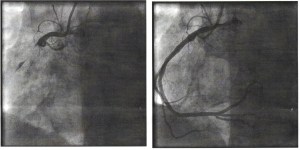

Here are the before and after photos of what my right coronary artery looked like in the space of a couple of seconds after the removal of the clot.